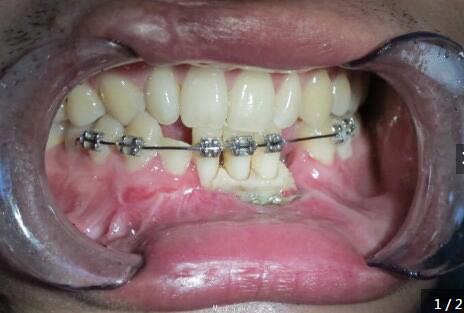

下颌前部可见唇与牙龈的撕裂、肿胀、牙松动,摇动损伤区的牙时,可见邻近数牙及骨折片随之移动,咬合错乱

下颌骨前部牙槽突骨折,下颌骨骨折 处理:托槽固定下颌牙槽突骨折,坚固固定内固定固定下颌骨骨折